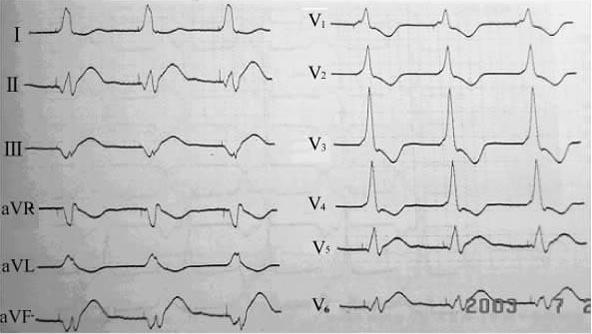

右心室心尖部通常作为右心室起搏的首选位置。由于右心室心尖部位于心脏前下方,该部位起搏时,心室除极方向为从心尖部向心底部,且右心室激动早于左心室,故体表心电图呈完全性左束支阻滞(CLBBB)图形,常伴以额面QRS电轴显着左偏(LAD,-30°~-90°)。因此,右心室心尖部起搏图形=LBBB+LAD。右心室心尖部起搏时,约一半患者V5、V6导联QRS波主波向上(图712)。另一半患者V5、V6导联QRS波主波向下或以S波为主(图713),说明心室除极的后半部分是自前向后的。

图7-1-2 右心室心尖部起搏心电图,起搏的QRS波呈LBBB+LAD,V5、V6导联QRS波主波向上

图7-1-3 右心室心尖部起搏心电图,起搏的QRS波呈LBBB+LAD,V5、V6导联QRS波主波向下